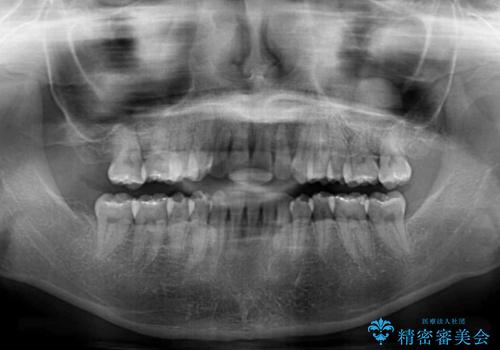

- 右上の八重歯と、左下八重歯を抜いてしまったことを気にして来院された患者様です。

下顎は既に犬歯を1本抜歯しているため、上顎右側第一小臼歯を抜歯し、ワイヤー装置にて歯列を整えることとしました。

変則的な抜歯となるため、正中と人中がずれる可能性がありましたが、仕上がりは上下正中を揃えることができました。